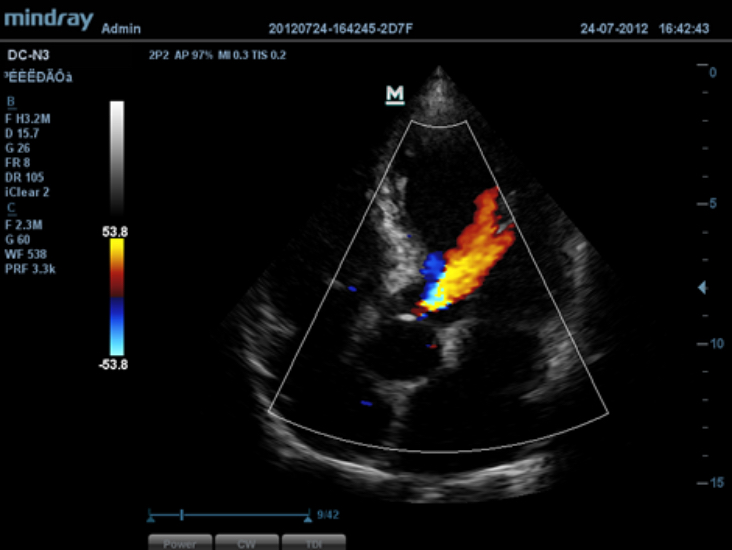

iBeam?

Memungkinkan penggunaan beberapa sudut pemindaian sekaligus untuk membentuk suatu gambar tunggal, sehingga meningkatkan resolusi kontras dan visualisasi.